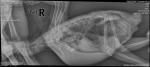

w1z Опубликовано 20 октября, 2017 Автор #23 Опубликовано 20 октября, 2017 Добрый вечер.Сделали рентген. Нужна помощь в расшифровке. Спасибо.

w1z Опубликовано 20 октября, 2017 Автор #25 Опубликовано 20 октября, 2017 Пожалуйста.http://vfl.ru/fotos/9b0fceb319076520.htmlhttp://vfl.ru/fotos/727cfe8919076539.html

Zosia Опубликовано 21 октября, 2017 #29 Опубликовано 21 октября, 2017 Снимки у вас только в таком размытом варианте? По любому мне на почту zofia68@mail.ruНо даже по ним у меня зреет нехорошее подозрение или на аспергиллез (тогда вы попали на сумму, превыщающую стоимость птицы), или на микоплазмоз (что тоже не айс, но дешевле и короче лечение). Бальд делает и мазки... и посевы.Чтобы знать,чем вашу птицу травить- вориконазолом (4 месяца) или тилозином (2 месяца)- нужно дифференциирвоать диагноз... поэтмоу вам приедтся сдавать анализы на бактериальный и микологический посев. Аспергиллез- это бич жаконь.. на этот счет есть даже отдельаня тема в подфоруме жаководов.И микоплазмоз так же встерчается нередко. А симптоматика у них очень схожа. Так же вам потребуются местные антимикотики(нистатин или пимафуцин), пробиотики (разные,будете подбирать под себя), антигистаминные препараты,гепатопротекторы(от карсила до гептрала- все какие найдете), ингаляции (купить увлажнитель простой ультразвуковой),эуфиллин в ампулах, кардиопротекторы- на всякий случай- Сульфокамфокаин,Нитроглицерин в спрее, кордиамин жидкий, валокардин или валидол жидкий, ГКС- дексаметазон в ампулах, если анйдете вет.препарат Монклавит- в геле или в жидком виде- и его тоже.Ампульный глюканат или борглюканат кальция.Весы- постоянно котролировать вес птицы. Короче... полквартиры медикаментов. Но сначала- анализы. До анализов можно только ингалировать некоторые препараты (напишу в личку) и пить иммуностимуляторы- можно растительные.

Стерлиция Опубликовано 21 октября, 2017 #32 Опубликовано 21 октября, 2017 Симптомов аспергиллеза не наблюдается никаких (уж за три месяца было бы что нибудь) тяжёлое дыхание отдышка, хрипы, выделения из носа. Ничего подобного нет. Выделений из носа при аспергиллезе нет. Когда вы видите тяжелое дыхание, сами слышите уже хрипы и сипы при дыхании птицы - это крайняя стадия. Чаще всего аспергиллез молчит. Снимки я бы посчитала не информативными.

w1z Опубликовано 22 октября, 2017 Автор #33 Опубликовано 22 октября, 2017 Хорошо, допустим снимки не информативные. Хотя не пересвеченные и достаточно контрастные (мне как не профессионалу так кажется).Дайте ссылку на те снимки, которые Вас устроили (есть наверное такие?) Я их покажу рентгенологу и скажу хочу такое же.Хотя мне в общем-то не совсем понятна позиция игнорирования ГЛАВНЫХ симптомов из-за которых и создавалась тема.

Zosia Опубликовано 22 октября, 2017 #36 Опубликовано 22 октября, 2017 https://fotki.yandex.ru/next/users/sangushk.../1454579?page=0 https://fotki.yandex.ru/next/users/sangushk.../1454600?page=0 https://fotki.yandex.ru/next/users/sangushk.../1454611?page=0 https://fotki.yandex.ru/next/users/sangushk.../1454615?page=0 https://fotki.yandex.ru/next/users/sangushk.../1454628?page=0 Снимки сдалны в разных клиниках,на разных птицах. У всех кроме сорочонка- аспергиллез. И добавлю.По тому анамнезу,что вы озвучили- ваша птица иммуноскопрометирована.И был грибок(какой?).На снимках- есть признаки гранулем.Остаточные это формы (бывшая инфекция из "большой тройки", или вполне себе активные зоны повреждения- я сказать не могу.То что ощипывается- часть является признаком аспера или микоплазмоза- т.к. микоплазмозные слепки или аспргилломы могут давать неприятные ощущения(при движении,при учащенном дыхании), а птица не понимает где у неё "свербит"- и пытается удалить беспокоящеее её место.Но этов се из области догадок. Выше я все уже вам написала.

Стерлиция Опубликовано 22 октября, 2017 #38 Опубликовано 22 октября, 2017 w1z, у вас уехал рентген, скорее всего птицу не зафиксировали нормально. На снимке позвоночник и киль должны быть ровными. Птица вытянутая,если во время снимка дернулась надо переснимать.